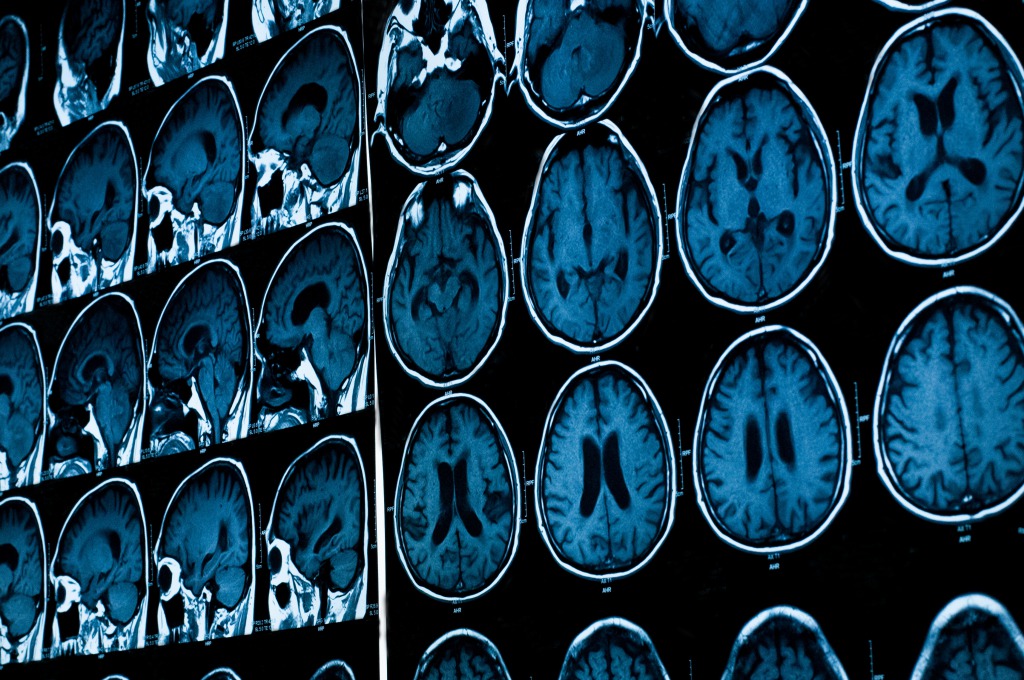

とはいえ、大量の飲酒が続くと、脳が徐々に縮み脳萎縮が進んでしまうことが研究からわかっています。

特に、物事の判断や意思決定に関わる「前頭葉」に与える影響が大きく、前頭葉で萎縮がおきると、物事の判断をしにくくなってしまうのです。

さらに、研究ではアルコールによる脳萎縮が将来の「認知症」の原因となる場合もあり、施設に入所している認知症高齢者の29%は大量飲酒が原因の認知症と考えられたという調査結果もあります。

結果、アルコールの摂取が前頭前野、前頭内側皮質や、側頭葉、頭頂間溝、頭頂内側領域などの脳の厚みの減少に関連していたことがわかりました。

一方で、大麻の使用は脳の厚さとの有意な関連は観察されず、脳への悪影響は見受けられませんでした。